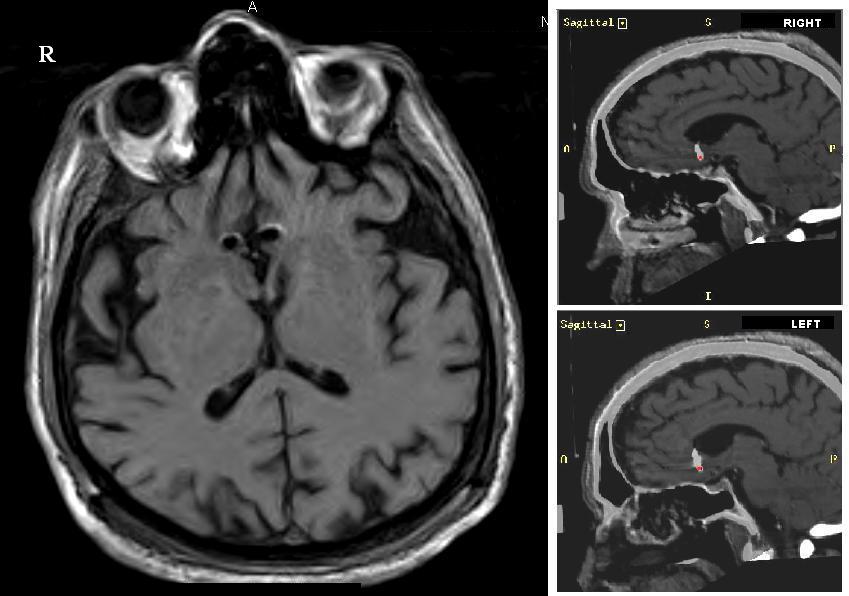

accumbens

ocd